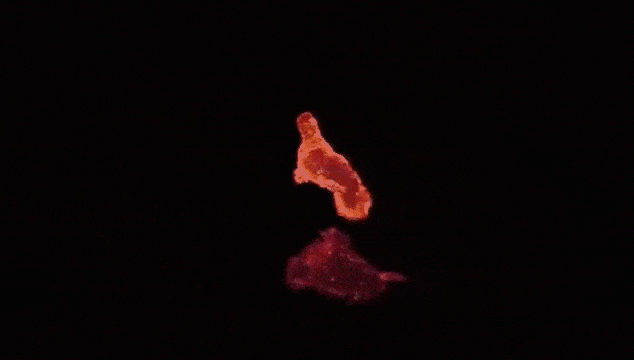

火山狀的乳癌細胞,正“騎”在它頭上的是經過修飾的CAR-T細胞,后者可以識別惡性腫瘤細胞。

一旦發(fā)現(xiàn)乳腺癌細胞,CAR-T細胞就會對其進行攻擊,從而減小腫瘤體積。